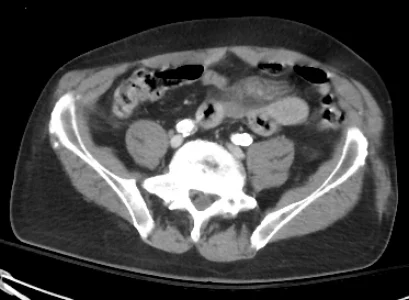

TRAUMA EMBOLIZATION: Case 2

55 year old male patient with abdominal pain s/p motorcycle accident.